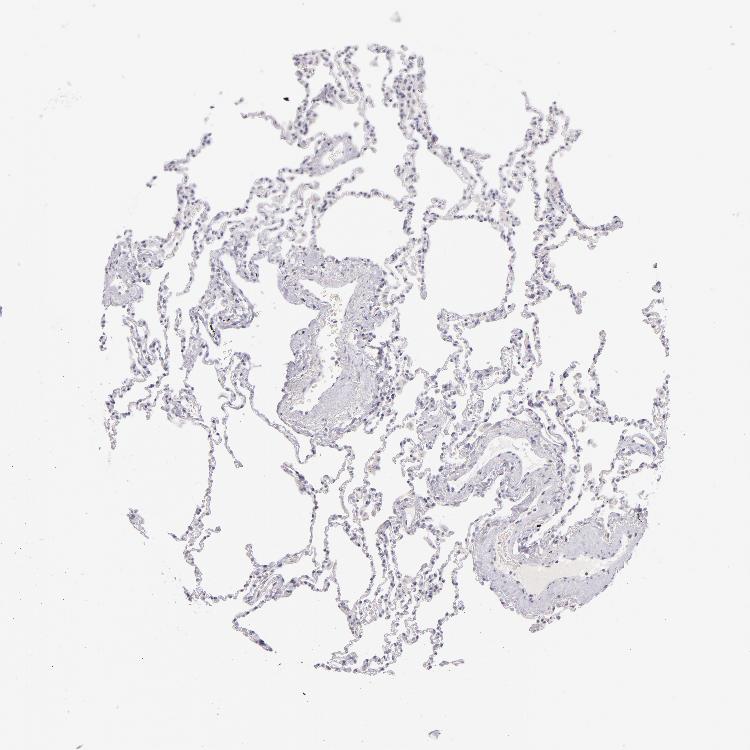

LUNG - Antibody stainingi

Antibody staining in the annotated cell types in the current human tissue is reported as not detected, low, medium, or high, based on conventional immunohistochemistry profiling in selected tissues. This score is based on the combination of the staining intensity and fraction of stained cells.

Each image is clickable and will lead to virtual microscopy that enables deeper exploration of all samples and also displays staining intensity scores, fraction scores and subcellular localization as well as patient and tissue information for each sample.

Antibody HPA031567Antibody HPA031568Antibody CAB002495Antibody CAB072868

Alveolar cells Not detectedNot detectedNot detected-

Alveolar cells type I ---Not detected

Alveolar cells type II ---Not detected

Endothelial cells ---Not detected

Macrophages LowMediumNot detectedMedium